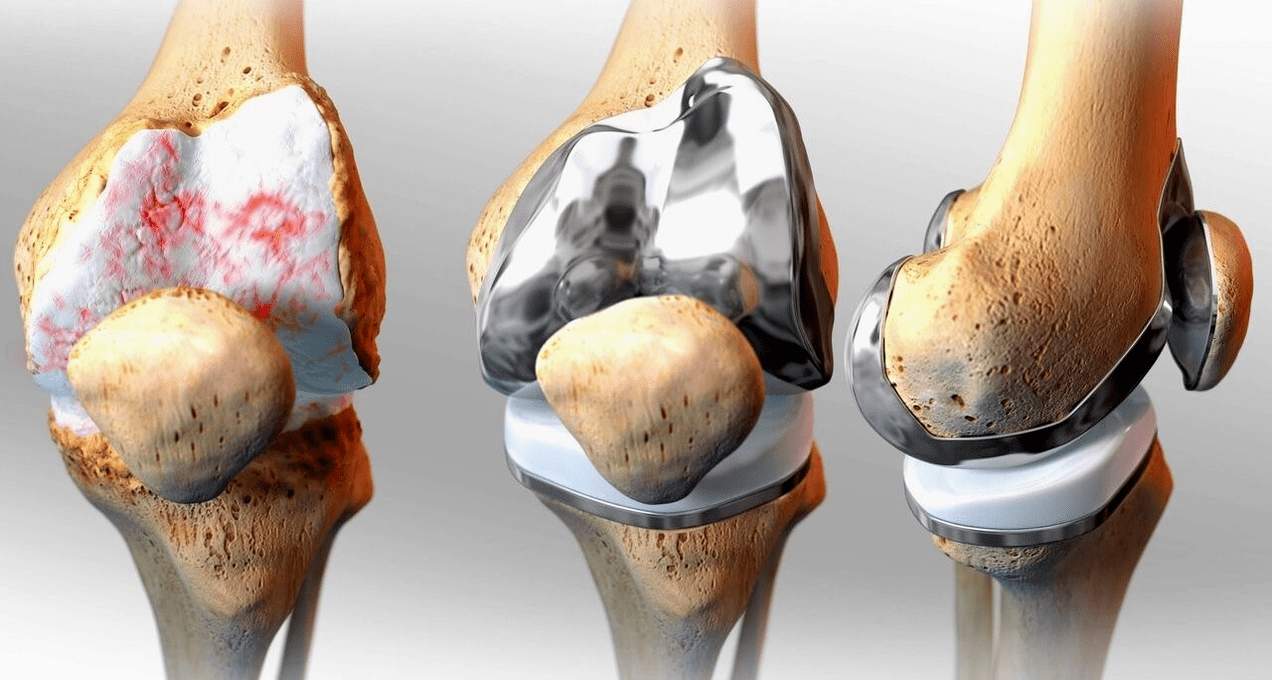

Surgical — arthroscopy (a low-traumatic method of treating intra-articular pathologies and removing damaged structures), endoprosthetics.

Replacement of the endoprosthesis is a common and effective surgical method for the treatment of severe gonarthrosis, which allows to preserve the mobility of the limbs and the ability to lead a full life later.It's a high-tech operation that takes about an hour and a half.In the postoperative period, long-term rehabilitation and development of the joint is necessary.After 25-30 years, when the artificial joint wears out, it needs to be replaced again.

knee replacement